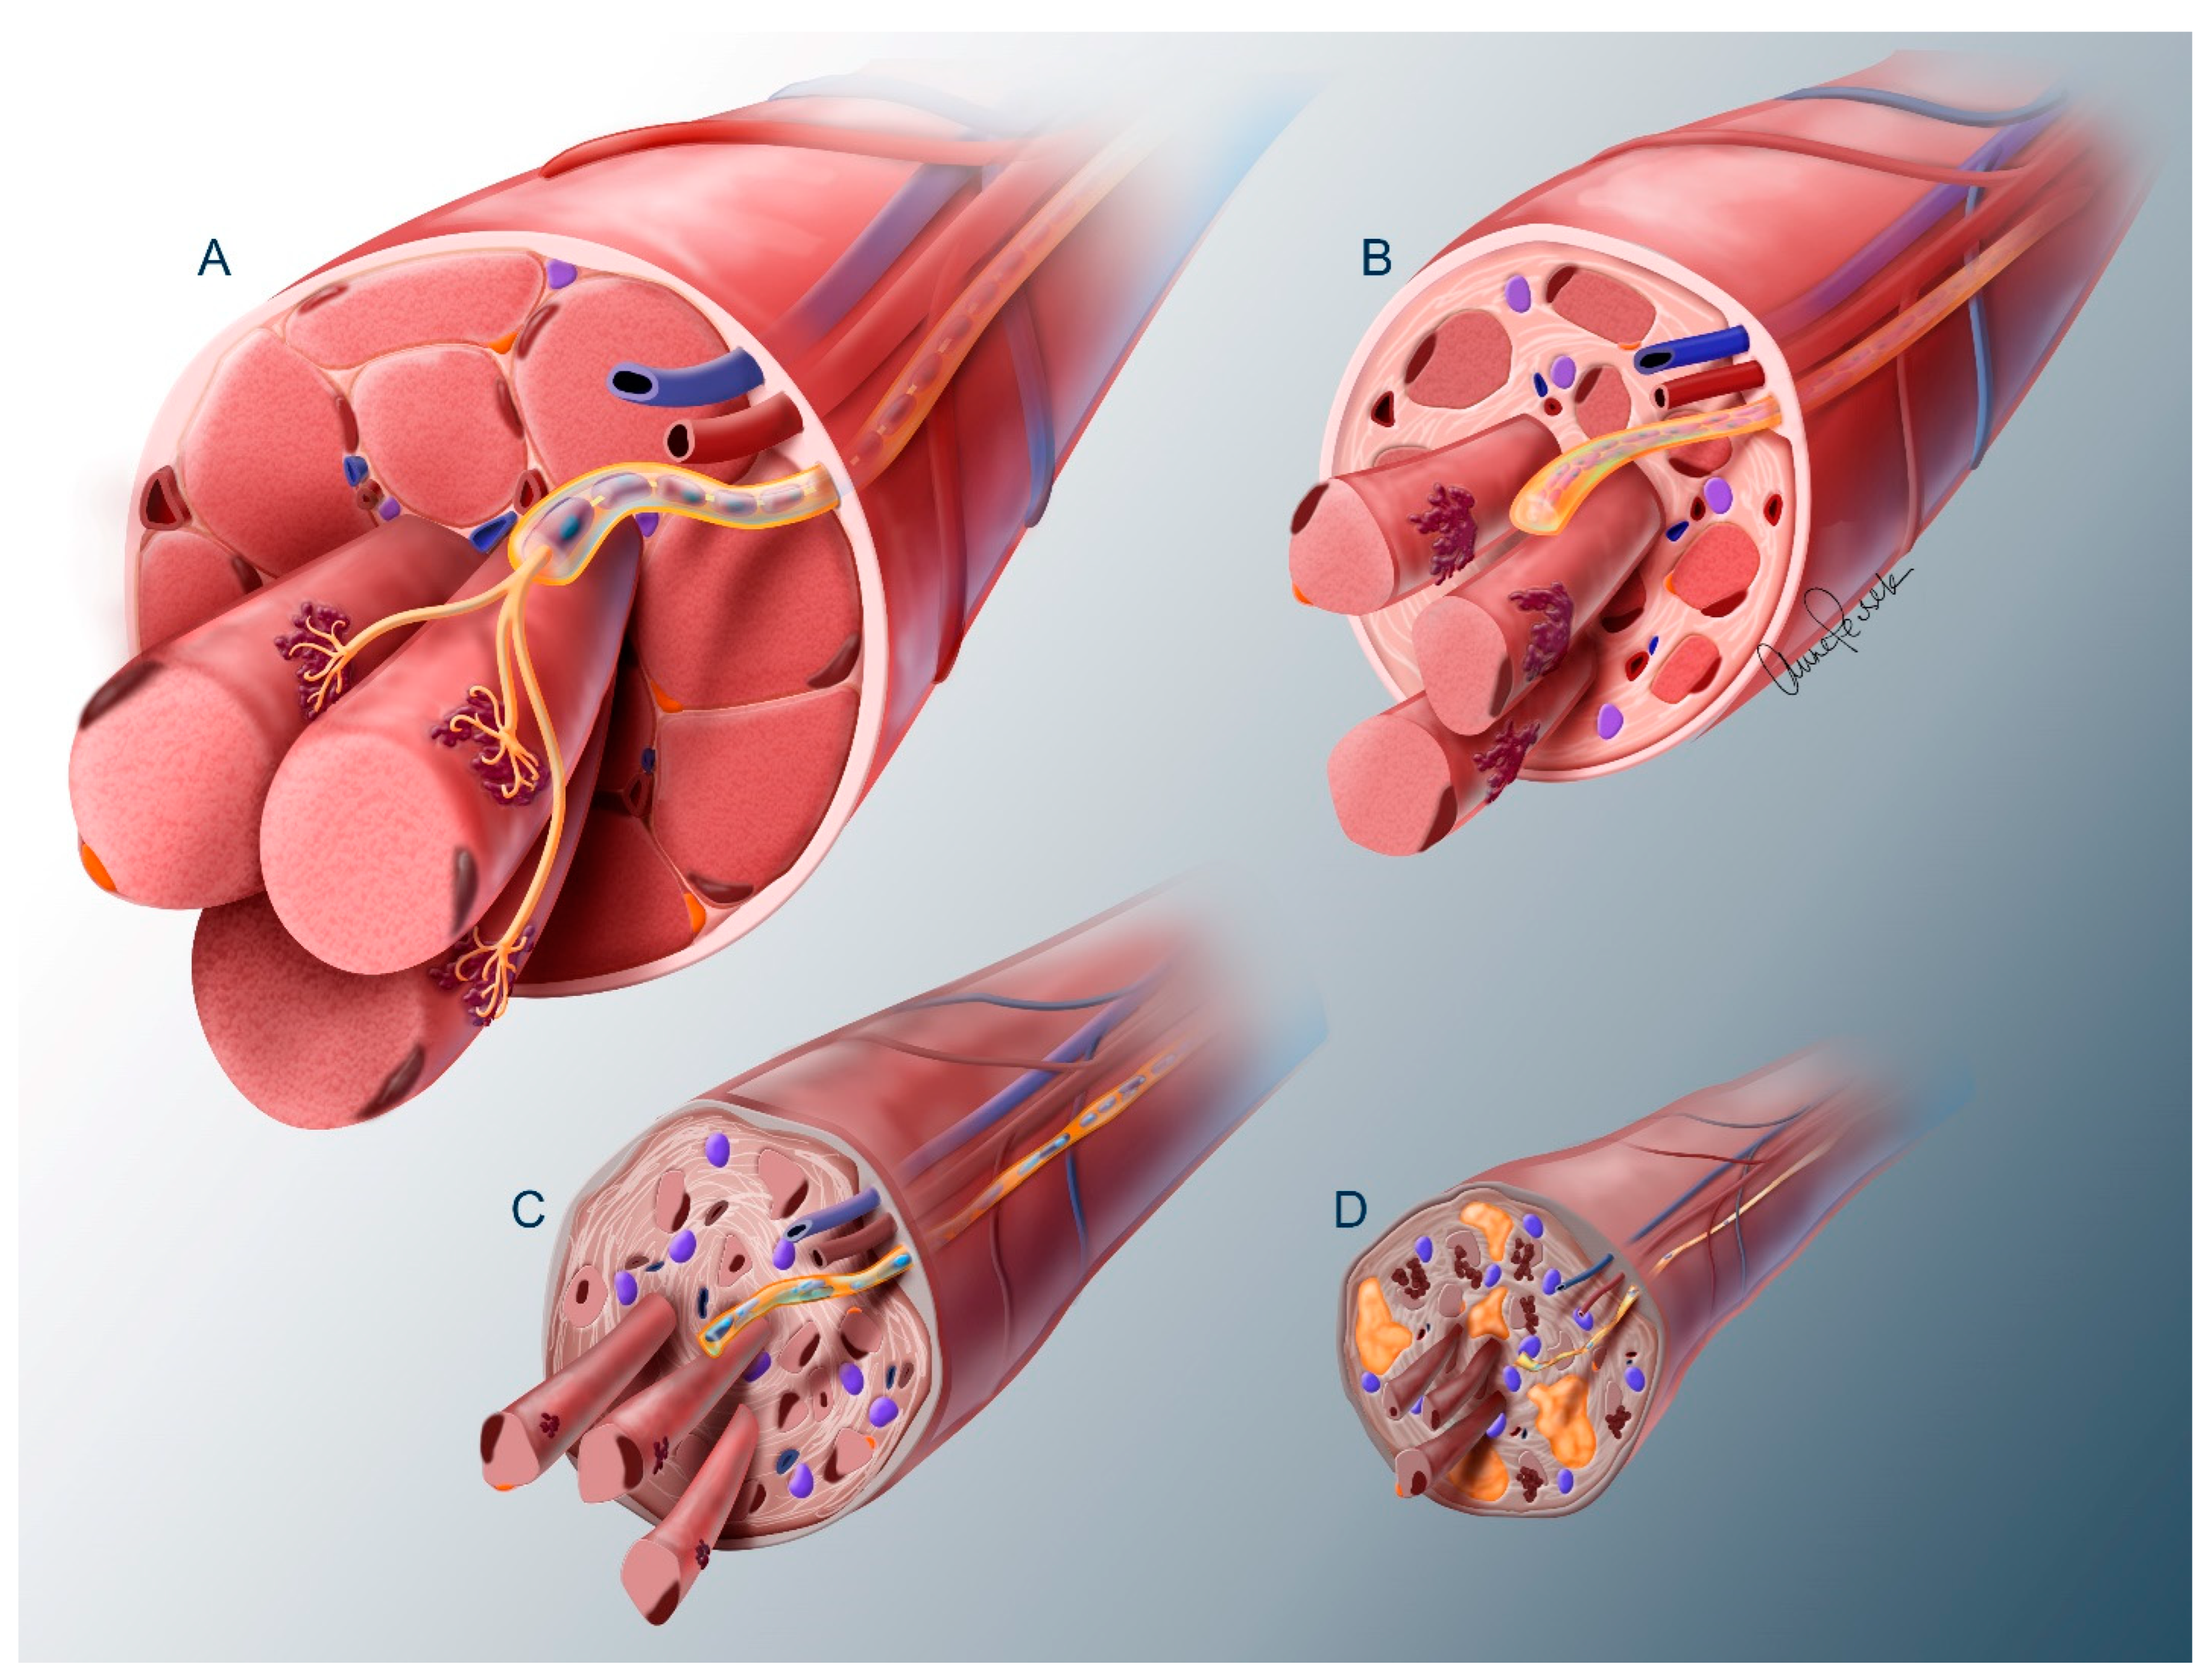

2. The Problem of Denervation Atrophy

2.1. Nerve Trunk

2.2. Neuromuscular Junction

2.3. Muscle